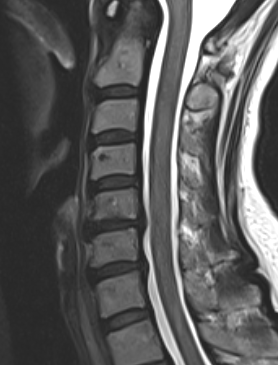

MRI

Degenerative disc changes

- dessication (loss of fluid)

- narrowing

- end plate changes

End plate changes Disc dessication with disc bulge